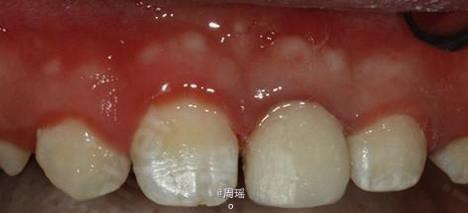

21冠折的树脂充填

树脂充填

效果很好,患者满意。